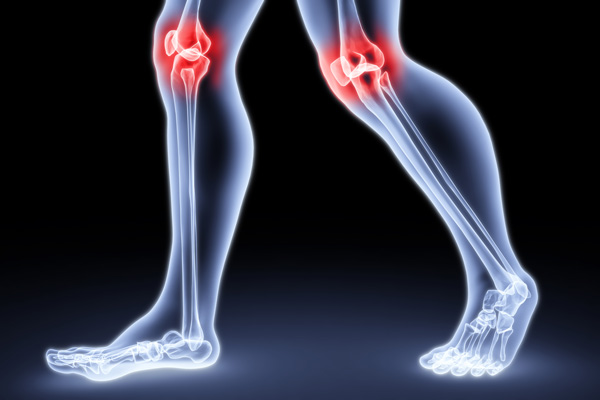

1. Ízületi fájdalmak, ízületi gyulladás, reuma

A tanulmányt – miszerint a kollagén bizonyítottan képes javítani az olyan degeneratív állapotokat, mint a porckopás, az ízületi gyulladás, illetve annak egy reumás változata - a Medscape orvosi magazinban is közölték.

Rávilágítottak, hogy létezik egy kritikus fehérjére, mely fokozatosan errodálja (rongálja, bontja) a porcot és a csontokat. E „romboló közvetítők” közé tartoznak a citokinek és egyéb fehérjebontó enzimek (a gyulladásban lévő sejtek), melyeket együttesen rövidítve MMP-nek (mátrix-metalloproteinázoknak) neveznek. Az ördögi kör azonban ott kezdődik, mikor ezek a gyulladásos sejtek behatolnak az ízületeket „kibélelő” szövetbe, és itt kezdik el szívni a sejtek elől az oxigént. (Ezt hívjuk magyarul oxidatív stressznek, hétköznapi nyelven pedig öregedésnek.)

A II-es típusú kollagént (mely elsődlegesen a porcok és az ízületek egyik fontos alkotóeleme) a Londoni Egyetem kutatói több szemszögből is vizsgálni kezdték krónikus, autoimmun betegség okozta ízületi gyulladásban szenvedő páciensek részvételével.

Az Arthritis & Rheumatism 2005. decemberi számában közölt eredmények tehát alátámasztják, hogy a II-es típusú kollagén potenciálisan hozzájárulhat a reumatikus ízületi gyulladás pusztító progresszióhoz.